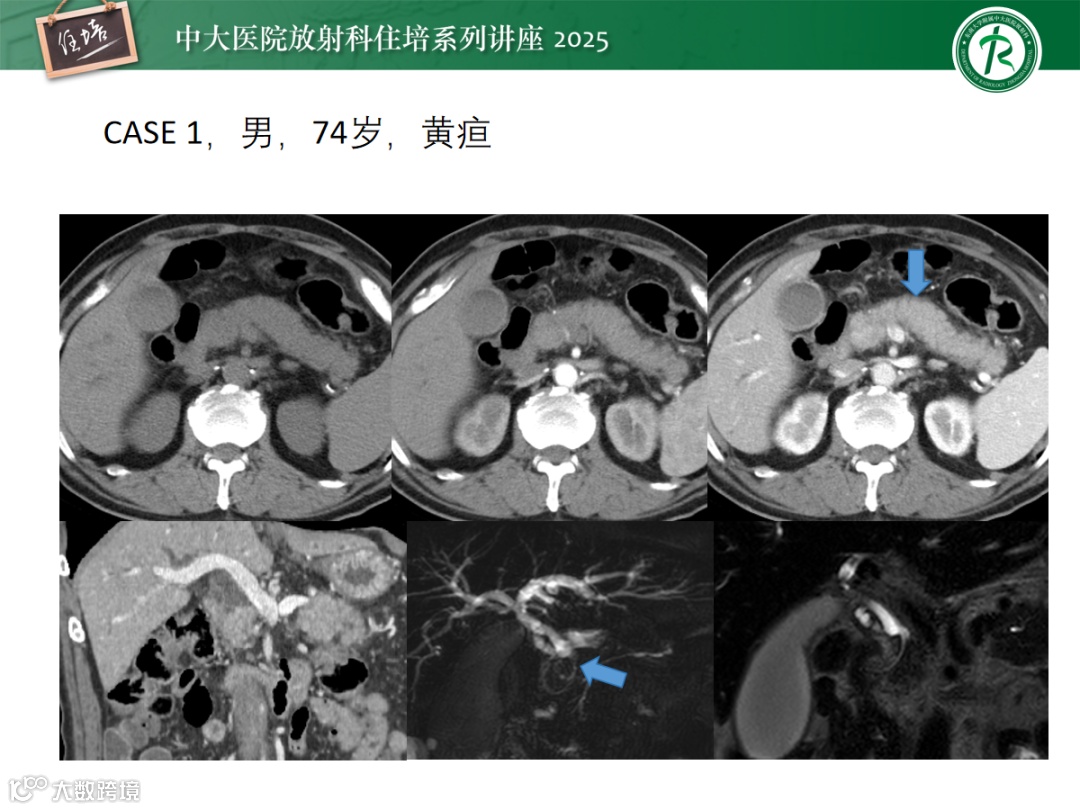

硬化性胆管炎的影像诊断与鉴别

来源:东南大学附属中大医院放射科